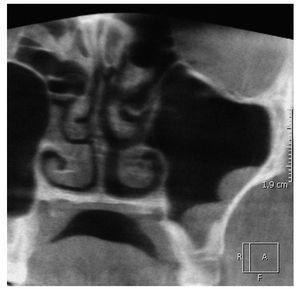

Caso 633, mujer, 36 años

Quiste radicular con origen en el diente 26

La paciente refirió en su visita a la consulta una ligera sensación opresiva en la zona del seno maxilar izquierdo de aproximadamente 4 a 5 semanas de evolución. En la radiografía panorámica obtenida se observó una imagen radioopaca redondeada, con un borde esclerótico, localizada en craneal del diente 26 (fig. 1). Desde el punto de vista radiológico, el diagnóstico apuntaba a un quiste radicular con origen en el diente 26. Sin embargo, en la exploración física, el diente mostró sensibilidad en la prueba de frío y no había evidencias de restauraciones previas ni de lesiones de caries.

Figura 1. Radiografía panorámica.

Se obtuvo una tomografía volumétrica digital dental del segundo cuadrante y del seno maxilar suprayacente para continuar el estudio diagnóstico. Por una parte, la TVD confirmó los resultados de la exploración clínica, según los cuales el diente 26 era un diente sano. Por otra parte mostró un ensanchamiento manifiesto de la mucosa basolateral del seno maxilar en craneal de los dientes 26 y 27. Este hallazgo sugirió la existencia de una sinusitis maxilar crónica con localización interseptal (figs. 2 a 4). Se observó además un desplazamiento parcial del orificio natural.

Figura 2. Tomografía volumétrica digital dental: plano axial.